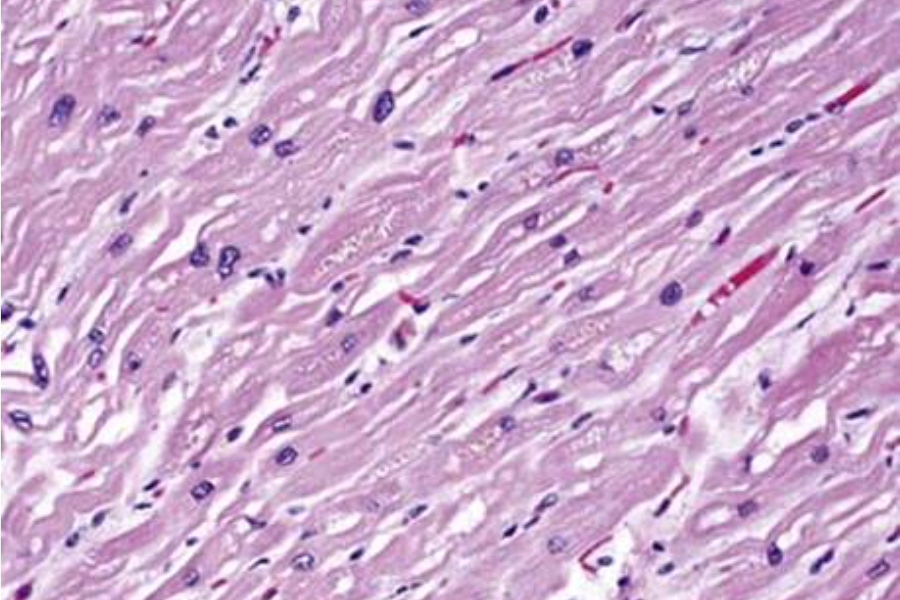

histologische Bilder

adultes Myokard

adultes Myokard

hypertensive Herzkrankheit

hypertensive Herzkrankheit

Pathology Residency and Fellowship Program, Brown University, Access 23. October 2022

Elliott P, McKenna WJ (2004) Lancet 363:1881-1891

Internet Pathology Laboratory , University of Utah, Access 23. October 2022

Thoracic Pathology, Cardiac Hemochromatosis, Access 23.October 2022